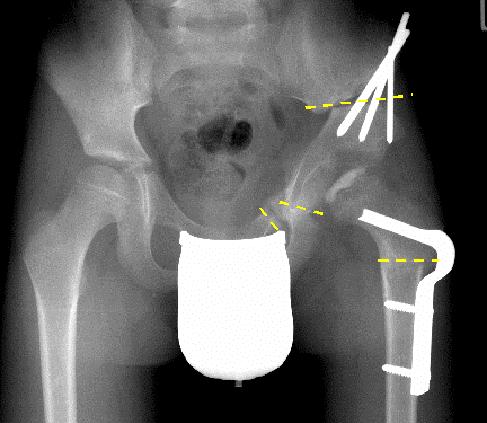

Zeigt sich bei den regelmäßig durchzuführenden Röntgenkontrollen, dass der Hüftkopf nicht gut in der Hüftgelenkspfanne zentriert ist, können operative Maßnahmen zur Verbesserung der Kongruenz zwischen Hüftkopf und –pfanne erforderlich sein. Diese werden entweder am Oberschenkelknochen durchgeführt (Varisationsosteotomie). Manchmal ist auch eine Korrektur der Pfannenposition (OP nach Salter, Tripleosteotomie des Beckens) erforderlich.